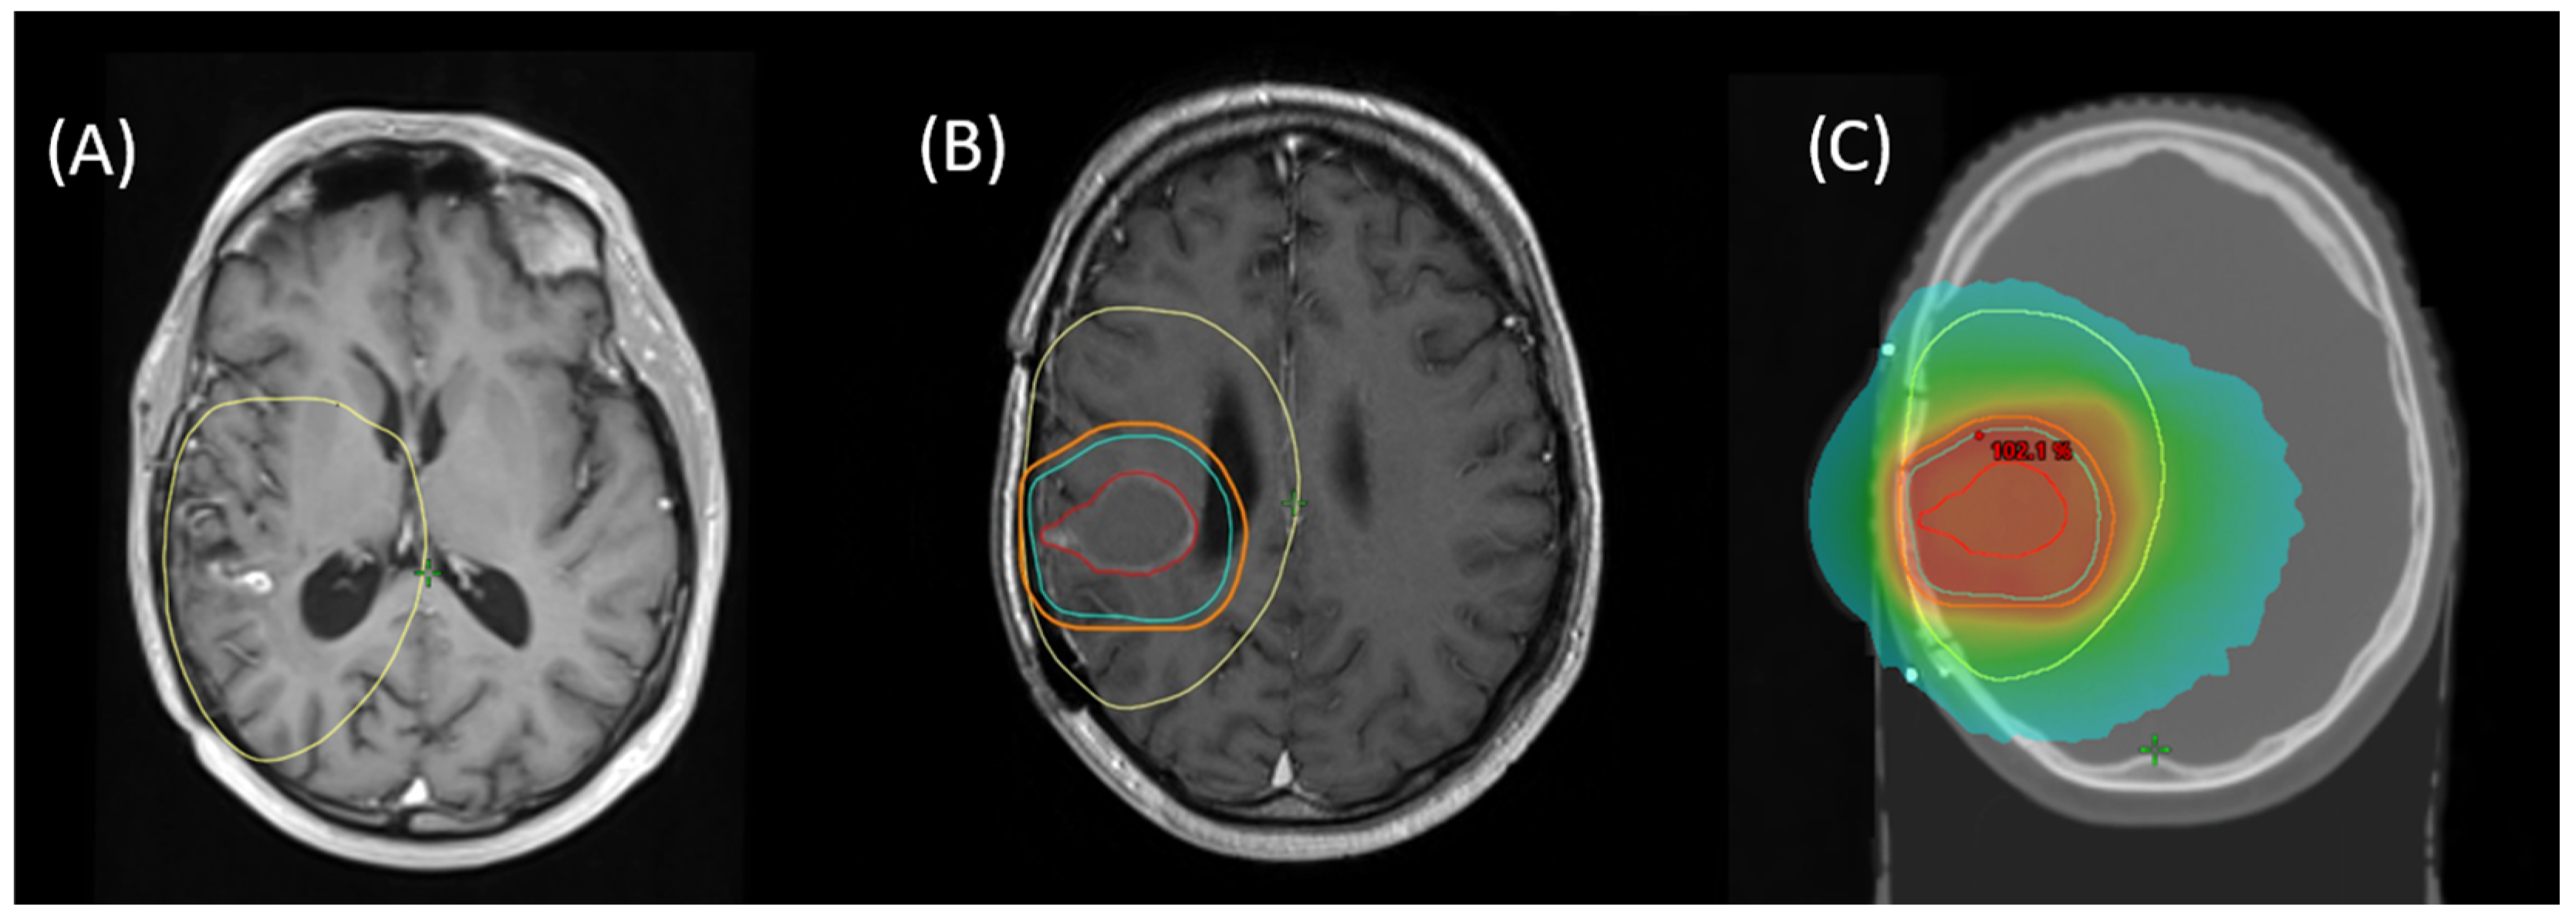

Re-RT planning was performed in accordance with ICRU8325. All patients were treated with 1.8–2 Gy daily fractions 5/week with IMRT-planning for conformal treatment volumes. All treatment plans and target volume definitions of patients included in this cohort were assessed. Treatment planning for all patients was realized via Varian Eclipse (by Varian medical systems, Palo Alto, CA, USA) or TomoTherapy® (by Accuray Inc., Sunnyvale, CA, USA). Diagnostic MRI was co-registered with the planning CT for all patients. Patients were treated with immobilization by a thermoplastic mask, using 6 MV or 15 MV Photons in different beam setups (Intensity Modulated Radiation Therapy [IMRT] or Volumetric Intensity Modulated Arc Therapy [VMAT], with helical therapy as a special form of VMAT). Re-RT target volumes were defined as standardized by ICRU50 with the gross tumor volume (GTV) enclosing the primary disease site (defined as sites of recurrent or progressing tumor after initial treatment, marked by blood–brain barrier disruptions in contrast-enhanced T1- and T2-MRI), the clinical target volume (CTV) incorporating sites of suspected subclinical infiltration (also considering the T2-FLAIR-signal if clinically appropriate), and the planning target volume (PTV) creating an additional margin to compensate for possible incongruences in patient positioning (usually 3–5 mm). For patients who received prior re-resection, the CTV was defined as areas of supposed residual tumor or associated with a high risk of subclinical infiltration, based on postoperative MRI (T2 and contrast-enhanced T1) with an additional margin, based on disease location and size, prior treatment, extent of resection, and clinical performance status. Postoperative patients with delayed initiation of radiation treatment (>3 weeks) received a dedicated planning MRI. An example for target volume definition and dose distribution is given in Figure 1.

Figure 1.

Example for (A) MRI of recurrent blood–brain barrier disruption of the right temporal lobe as a manifestation of recurrent glioblastoma, fused with initial RT planning CT to show first-line treatment PTV (yellow). (B) Planning MRI after surgical resection for fusion with planning CT with resulting target volumes for re-RT (GTV = red, CTV = cyan, PTV = orange). (C) Resulting cumulative dose distribution for re-irradiation with 39.6 Gy via helical therapy.